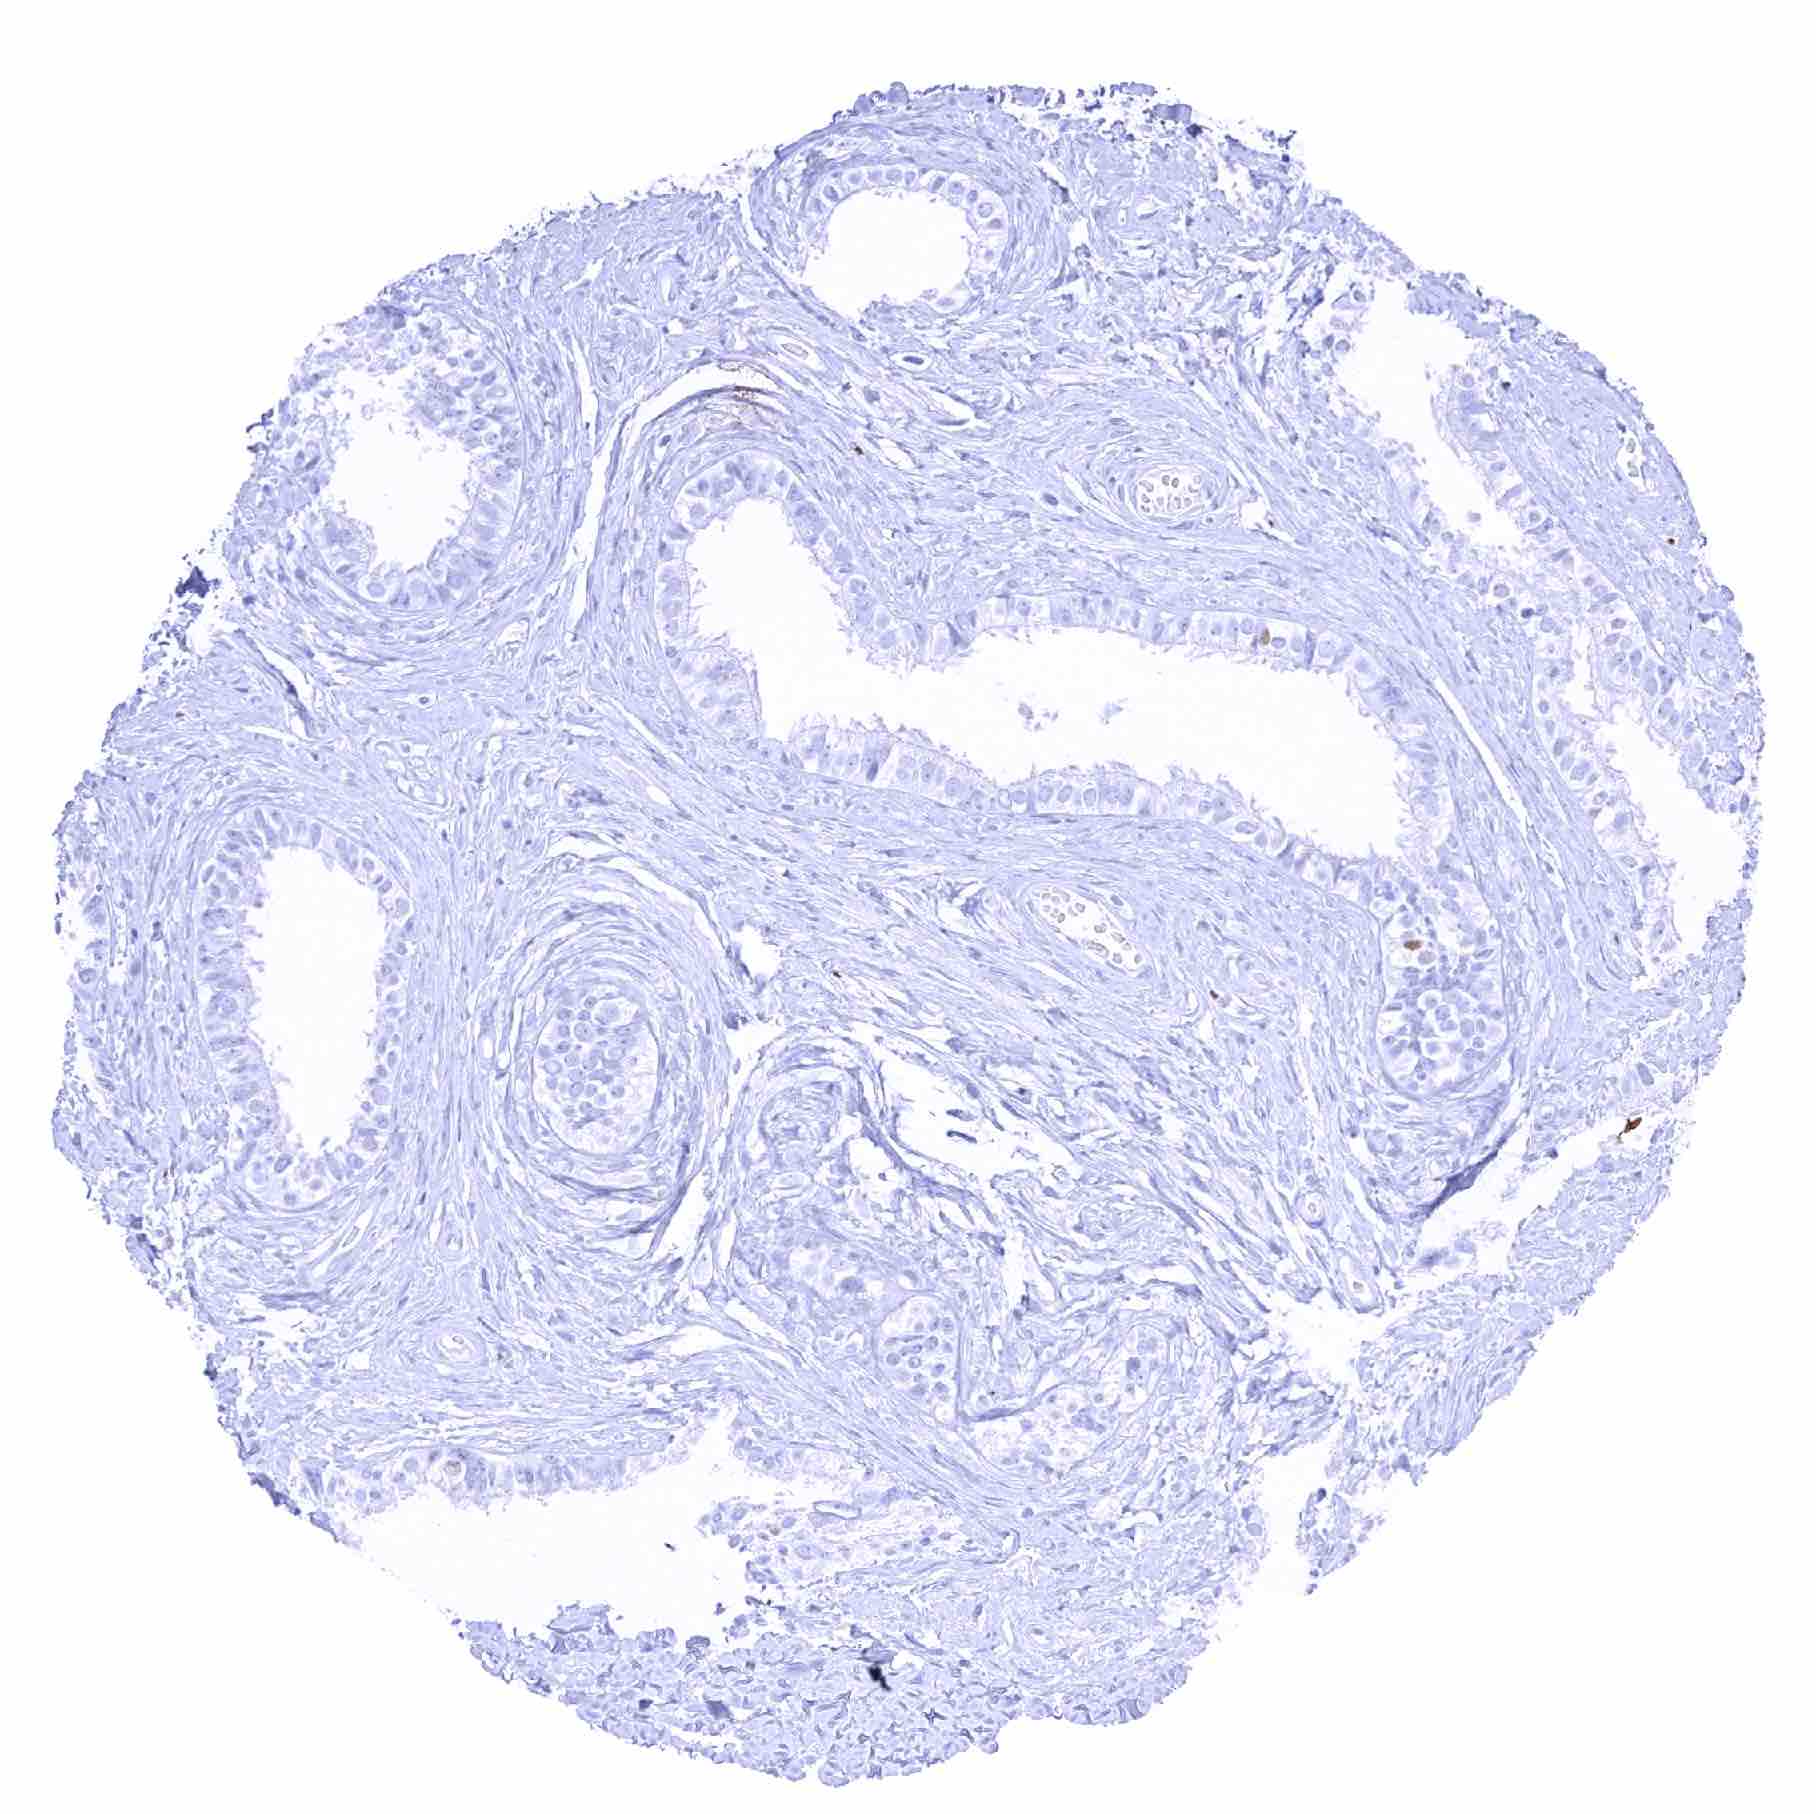

Uterus, ectocervix